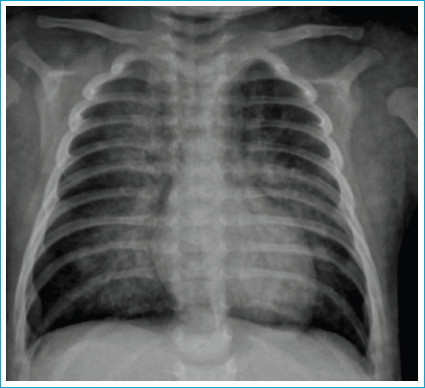

Among the agents used for self-defense, O-chlorobenzylidene malononitrile (CS) is the most commonly used substance. It has been suggested that CS use is characterized by rapid onset of action, short duration of action, and minimal side effects. When the clinical situations and case series resulting from exposure to CS were examined, we saw that no cases of exposure during the neonatal period were identified. A male baby born at 40 weeks, weighing 3260 grams, was brought to the emergency room on the 24th postnatal day with bruising and respiratory distress due to a stranger spraying CS into his mouth. There was a widespread hyperemic erosive lesion in the mouth, tongue exfoliation, and leg ecchymosis. Widespread edema and hyperemia were observed in the vocal cords, and the patient was intubated and followed up. An epithelial defect involving the corneal limbus and conjunctiva was detected in the upper and lower eyelid membranes. Endoscopy revealed a grade 2 burn in the esophagus, and normal pseudomembrane and gastric mucosa in some areas. It was observed that the lesions around the patient's mouth and tongue completely resolved. After discharge, the esophagus-stomach-duodenum radiograph showed no suspicion of obstruction. At the 3rd-month post-discharge check-up, his eye examination was normal, and his stridor and wheezing at rest continued. This case, in which we have shown that CS used for self-defense or riot suppression, seriously threatens the life of a newborn patient for the first time and may perhaps cause permanent morbidities during follow-up, suggests the need to restrict access to such substances.